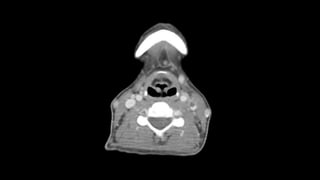

Una mujer de 31 años fue ingresada por faringoamigdalitis pultácea que no mejoró con tratamiento ambulatorio. Presentaba también molestias abdominales, náuseas, vómitos y diarrea. Las pruebas revelaron anemia grave, hipertransaminasemia e infiltrados pulmonares. El diagnóstico final fue bacteriemia por Fusobacterium necrophorum, trombosis de la vena yugular interna izquierda e infiltrados pulmonares, confirmando el síndrome de Lemierre.